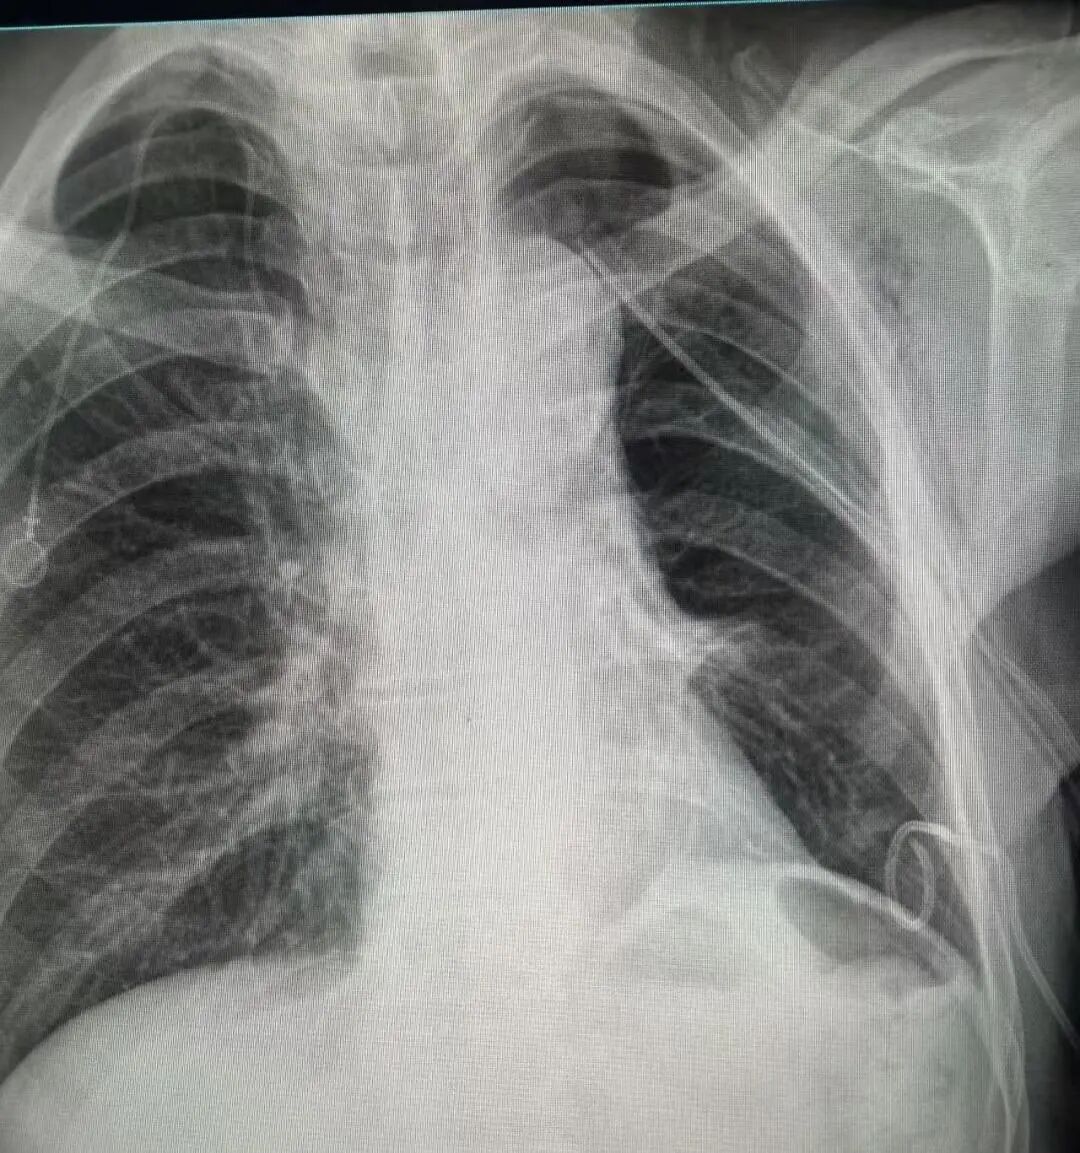

术后胸片

1-7.jpg

术后病理:切除组织未见残留癌细胞,达到根治效果